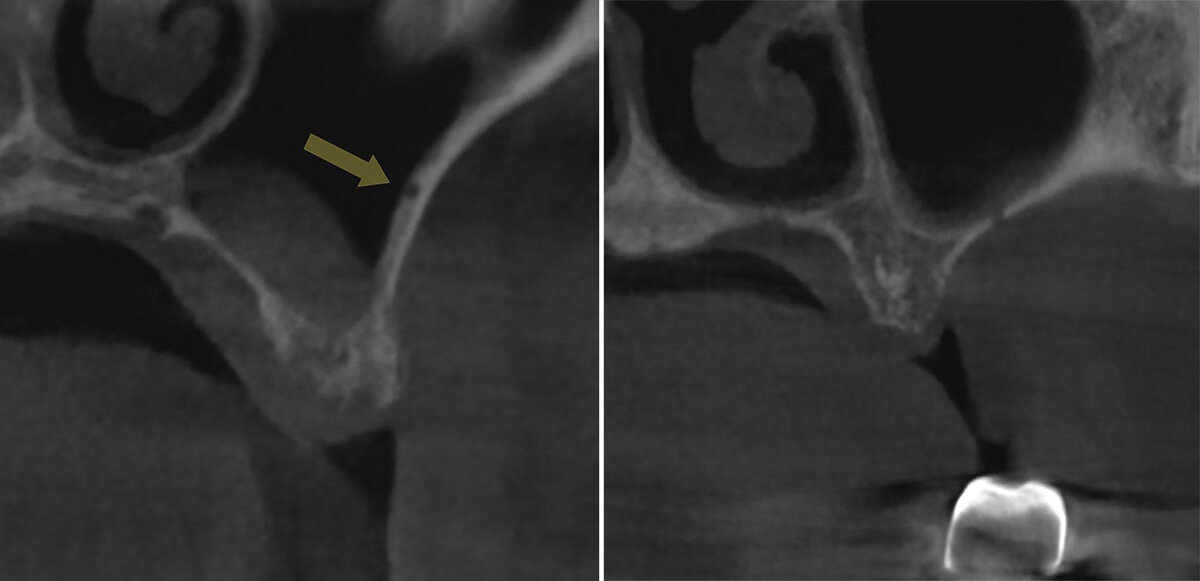

Для определения расположения ААА на КЛКТ важно выявить дискретный канал или вдавление в латеральной стенке верхнечелюстного синуса (рис 1.a, b) [2,16].

Рисунок 1. Рентгенологические признаки альвеоло-антральной артерии на коронарном реформате КЛКТ. a: вдавление в латеральной стенке верхнечелюстного синуса (стрелка);

b: прерывание стенки верхнечелюстного синуса.